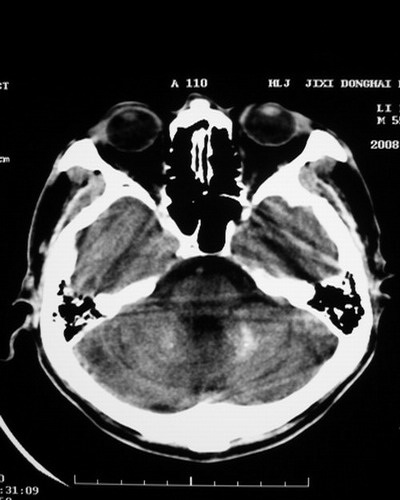

以下是引用随光逐影在2008-1-14 17:26:00的发言:[br]考虑为:甲状旁腺功能低下。需与fahr`s病相鉴别。建议:实验室检查。